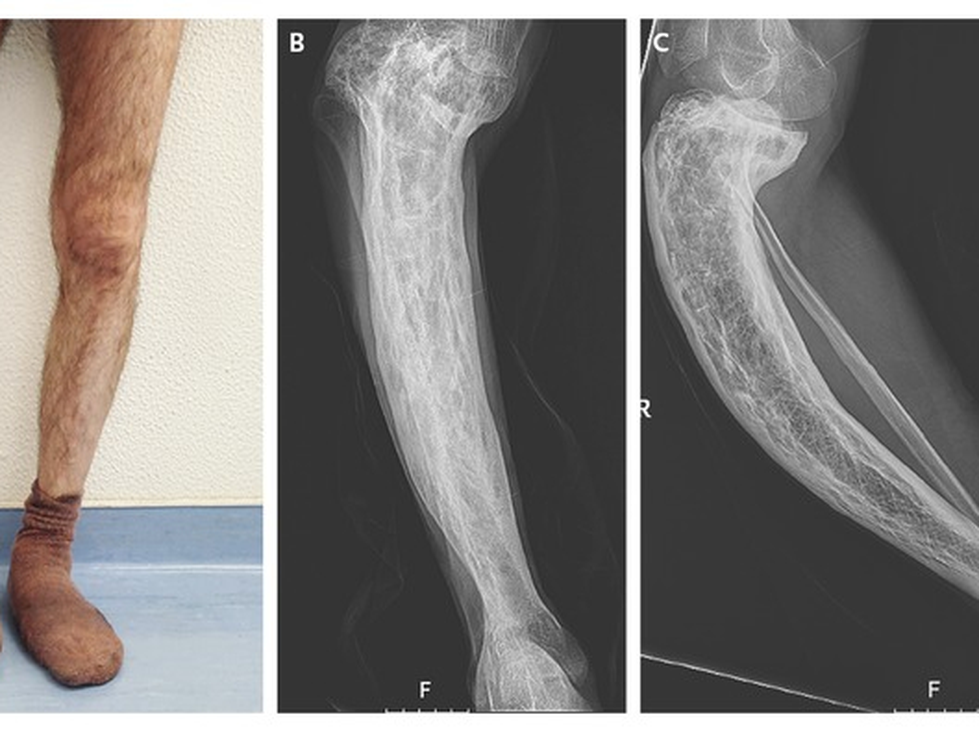

- Tăng kích thước đầu, cong chi hoặc cong cột sống. Điều này có thể xảy ra trong các trường hợp nâng cao.

- Gãy xương và dị tật: Xương bị ảnh hưởng dễ gãy hơn, và các mạch máu thừa trong những xương bị biến dạng này khiến chúng chảy máu nhiều hơn trong quá trình phẫu thuật. Xương chân có thể bị vòng kiềng, có thể ảnh hưởng đến khả năng đi lại.

- Chụp X-quang phần xương bị ảnh hưởng. Bệnh Paget hầu như luôn được chẩn đoán bằng chụp X-quang.